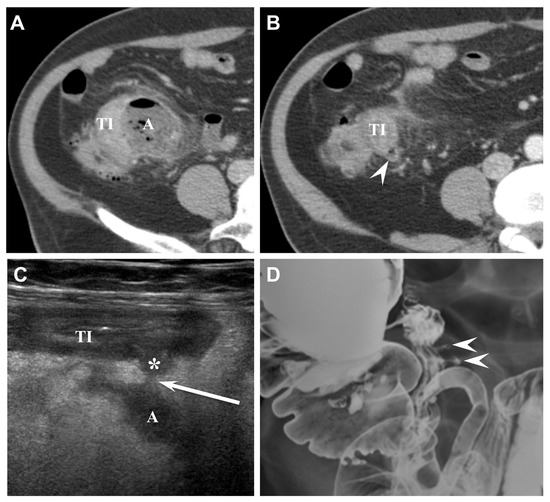

Figure 2. Sixty-seven-year-old male (patient #2) with acute perforated ileal diverticulitis. (A,B) Axial CT scans show ileal wall thickening (TI) with mesenteric abscess (A) and mesenteric fat infiltration. There is no definite inflamed diverticulum on CT. However, adjacent ileal diverticulum (arrowhead) supports the diagnosis of perforated ileal diverticulitis with abscess formation. (C) US scan with linear transducer reveals outpouching inflamed diverticulum (*) protruding from the terminal ileum (TI) and connecting to mesenteric abscess (A) with focal perforation site (arrow). (D) Barium study after 1 month shows two diverticula (arrowheads) protruding from the terminal ileum and multiple diverticula from the colon.

The CT findings for acute ileal diverticulitis are summarized in Table 2. All 17 patients had ileal diverticulum along the mesenteric border. Inflamed diverticulum was seen in 16 patients (94.1%) (Figure 1). The remaining patient did not have an inflamed diverticulum at the center of ileal wall thickening with abscess; however, adjacent ileal diverticula supported the diagnosis of acute ileal diverticulitis with perforation, and barium study after 1 month demonstrated two ileal diverticula along the mesenteric border (Figure 2). Three patients had radiodense fecalith within the inflamed diverticulum (Figure 3). All 17 patients had mesenteric fat infiltration with varying degrees and ileal wall thickening. Five patients (29.4%) were diagnosed with perforated ileal diverticulitis, which had the following findings: abscess (n = 2) (Figure 2), extraluminal fluid with air (n = 3) (Figure 4), and/or focal defect in the diverticular sac (n = 2) (Figure 5). Mesenteric venous gas (Figure 4) and mesenteric venous thrombosis were seen in two patients (11.8%), respectively.

The US findings for acute ileal diverticulitis are summarized in Table 3. All patients showed outpouching inflamed diverticular sac connecting to the ileum, peridiverticular inflamed fat presenting as hyperechoic fat around the diverticulum, and increased color flow to the diverticulum and surrounding inflamed fat on CDI (Figure 1). The inflamed diverticulum exhibited variable echogenicity (Figure 2 and Figure 3). Like CT findings, eight patients had a single diverticulum and nine patients had multiple diverticula. Unlike CT, US examinations diagnosed perforated ileal diverticulitis in seven patients. The findings indicated that five patients had both abscess and extraluminal air bubble (Figure 4 and Figure 5), one patient had only extraluminal air bubble (Figure 6), and one patient had only abscess.

Historically, acute ileal diverticulitis has been diagnosed on exploratory laparotomy for other challenging differential diagnoses [1,20]. The technological advances and widespread use of CT have enabled radiologists to play an essential role in diagnosing acute ileal diverticulitis [3,16,18]. The characteristic CT findings of acute ileal diverticulitis in this study included ileal wall thickening with small-sized inflamed diverticulum at the mesenteric side and surrounding mesenteric fat infiltration, which was consistent with CT findings in previous studies [3,4,5,6,7,8,9,10,11,13,16,18,24,30]. Especially, direct visualization of the inflamed diverticulum was the key feature in diagnosing acute ileal diverticulitis. Sixteen of 17 patients had direct visualization of inflamed diverticulum on CT. The remaining patient, who was diagnosed with perforated diverticulitis with abscess, did not show an inflamed diverticulum on CT. However, US demonstrated inflamed diverticulum protruding from the ileum and connecting with the abscess in the patient. We believe that US could play a complementary role if the inflamed diverticulum was not seen on CT.